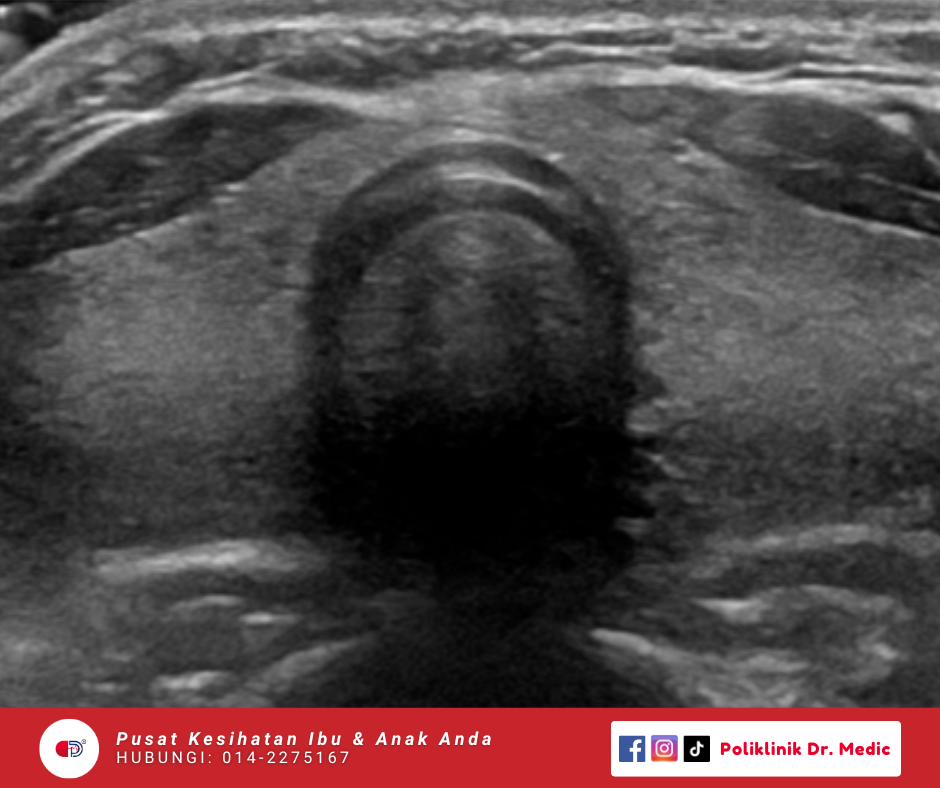

SCROTAL + TESTICAL Scan

Pemeriksaan testis dan struktur dalam skrotum termasuk saluran sperma serta pembuluh darah bagi mengenal pasti punca sakit atau ketidakselesaan. Pemeriksaan ini dapat mengesan awal keadaan seperti sakit berterusan, bengkak, perubahan saiz testis.

RM90